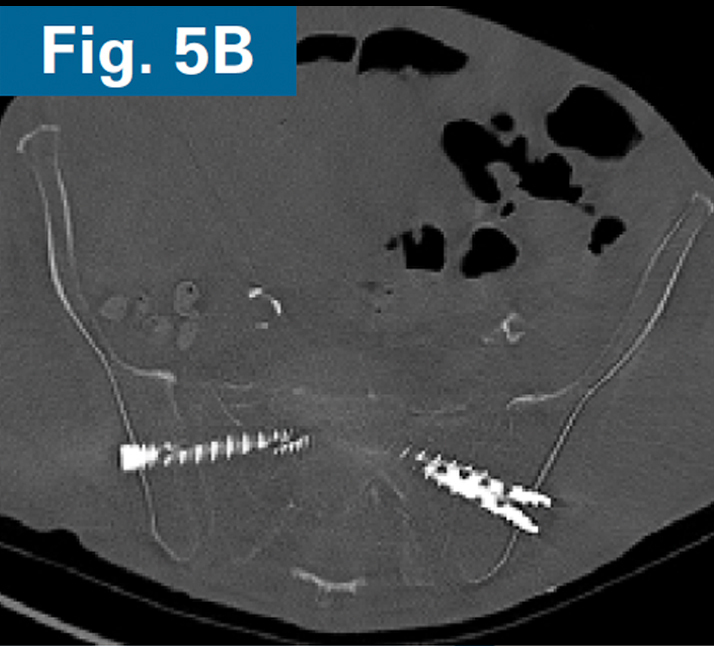

• Immediate postoperative CT scan demonstrate safe placement of implants (Figs. 5A and 5B).

• AP and standing lateral sacral view at 3 months follow-up.

• Callous formation noted on the lateral radiograph (Figs. 6A and 6B).

• Clinically, the patient is ambulating comfortably and is not requiring opioids.4